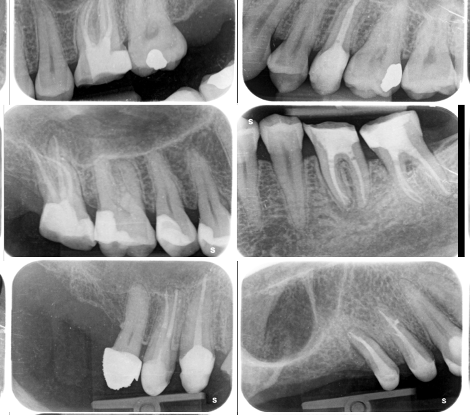

• Příklady z praxe (RTG snímky, klinické kazuistiky)

• RTG vs. CBCT – co, kdy a proč